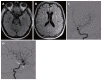

Traumatic injuries of the carotid artery may result in severe morbidity and mortality. The most common location of carotid artery injury is the cavernous segment, which may result in fistulous connection to the cavernous sinus and ophthalmic veins, which in turn lead to pressure symptoms in the ipsilateral orbit. Unlike the commonly reported direct traumatic carotid-cavernous fistula, we describe an unusual case of a 38-year-old man presented with a traumatic brain injury led to a fistula connection between the cavernous carotid artery and the ipsilateral basal vein of Rosenthal, with eventual drainage to the straight and transverse sinuses. The basal vein of Rosenthal is usually formed from confluence of anterior and middle cerebral veins deep in the Sylvian fissure and drain the insular cortex and the cerebral peduncles to the vein of Galen. Immediate endovascular deployment of a covered stent in the cavernous carotid artery allowed sealing the laceration site. Three months follow up showed a non-focal neurological examination and healed carotid laceration over the covered stent.